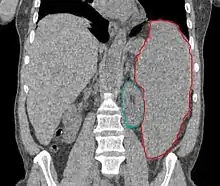

سندرم میلودیسپلاستیک (Myelodysplastic Syndromes - MDS) ناهنجاری در تقسیم سلول بنیادی خون بوده از نظر کمی و کیفی در نقصان تولید سلولهای خونی نقش دارد. MDS در کمخونیای که نیاز به تزریق خون مزمن داشته باشد دیده میشود. در بیشتر مواقع به دلیل افزایش نارسایی مغز استخوان هر یک از سلولهای خونی گویچه سرخ، گویچه سفید یا پلاکت دچار کاهش تولید میشوند.